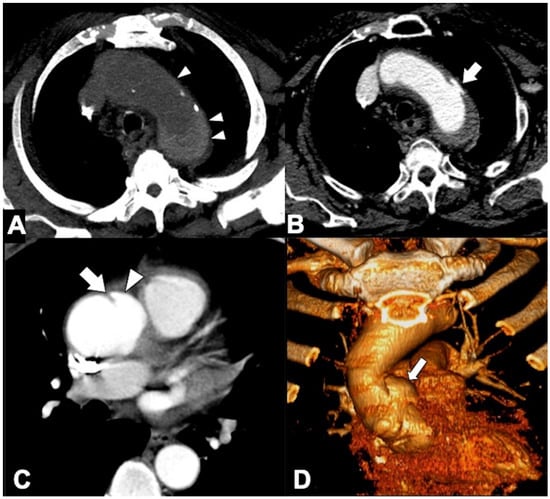

| Location | CTA Findings | Complete Rupture | Impending Rupture |

|---|---|---|---|

| Intramural | Increased aneurysm (>5.5 cm) | - | + |

| Rapid enlargement rate (>4 mm/year) | - | + | |

| Focal wall irregularity | + | + | |

| Hyperattenuating crescent sign | - | + | |

| Thrombus fissuration | - | + | |

| Draped Aorta sign | - | + | |

| Missing calcium sign | - | + | |

| Tangential calcium sign | - | + | |

| Luminal | Aortoesophageal fistula | + | - |

| Aortobronchial fistula | + | - | |

| Periaortic stranding | - | + | |

| Extraluminal | Contrast extravasation | + | - |

| Mediastinal hematoma | + | - | |

| Pleural hematoma | + | - | |

| Pericardial hematoma | + | ± |